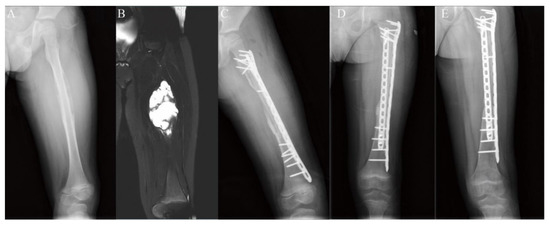

3.2. Lower Extremity Reconstruction Results